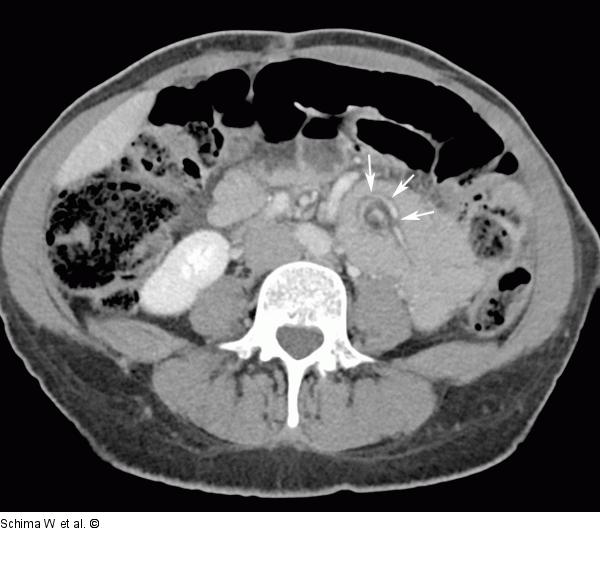

Abbildung 1a: MDCT Die Kontrastmittel-verstärkte MDCT zeigt die Rotation der mesenterialen Gefäße um die eigene Achse („Whirl Sign“) (Pfeile). |

Die Kontrastmittel-verstärkte MDCT zeigt die Rotation der mesenterialen Gefäße um die eigene Achse („Whirl Sign“) (Pfeile). |